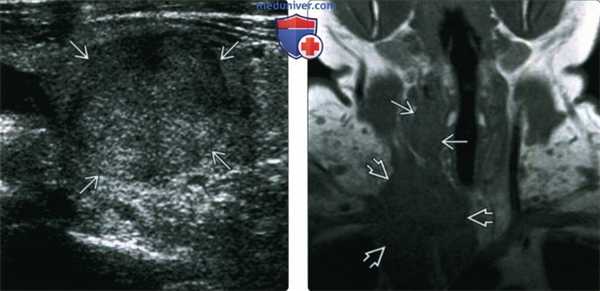

(Слева) УЗИ в продольной проекции. В щитовидной железе определяется солидное образование с четкими контурами и гипоэхогенным гало. Какие-то специфические признаки, которые бы позволили отличить опухоль от аденомы или дифференцированной карциномы, отсутствуют.

(Справа) При МРТ Т1ВИ в коронарной проекции у пациента, которому выполнена тиреоидэктомия по поводу спорадического медуллярного рака щитовидной железы, справа, в ложе щитовидной железы определяются признаки рецидива. Крупная инфильтрирующая опухоль спускается в верхнее средостение, окружает сосуды и сдавливает правую яремную вену. Образование является рецидивом медуллярного рака.